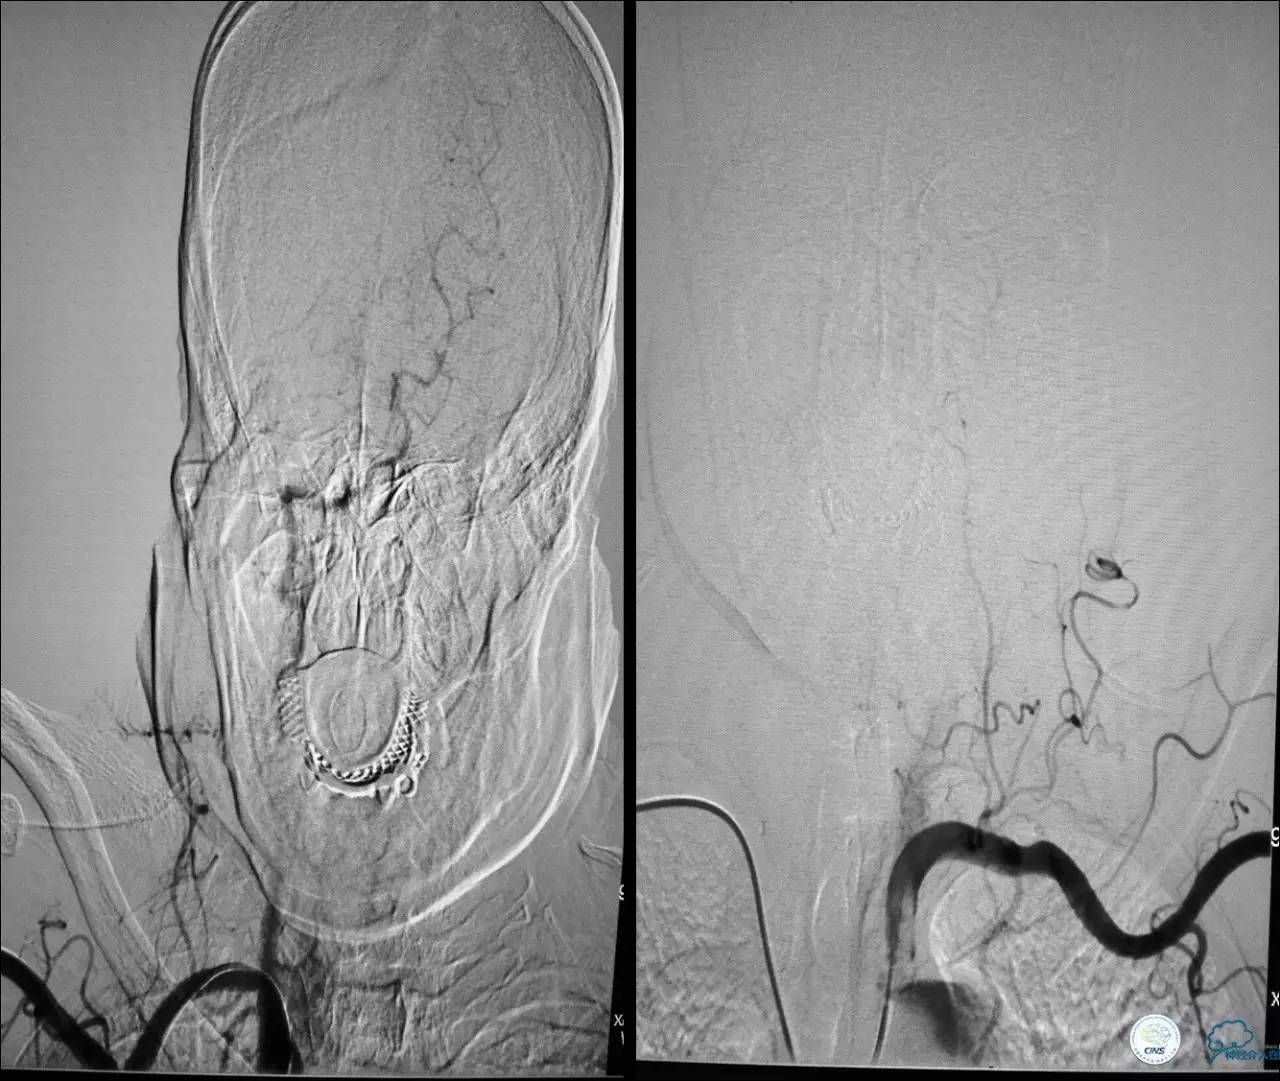

术中技巧

》当成颈动脉闭塞开通做,同时8F鞘内套以4F鞘给予微导管足够支撑力。

》避免后扩,分次治疗。

》术中脑保护,首选SPIDER。

★脑保护技术:病死率及卒中率从7.9%~9.1%降至1.7%,已作为CAS治疗常规。

远端滤网保护装置

滤膜网孔Φ为80~130 m,主要优点是不阻断血流,适合于绝大多数患者,能够在手术中随时造影监测操作步骤。

滤器缺陷:

◆不能提供全程保护;

◆推送的外鞘管有较大的外径和硬度,超选及通过严重迂曲狭窄的操作相对困难;

◆滤器无法过滤小于网孔直径的碎片;

◆滤器对血管内膜机械损伤 。

Spider FX™特点

导丝先行技术,目前通过性最好的远端栓塞保护装置。

术者可以选择“最顺手”、“最合适”的导丝辅助SpiderFX™通过病变。